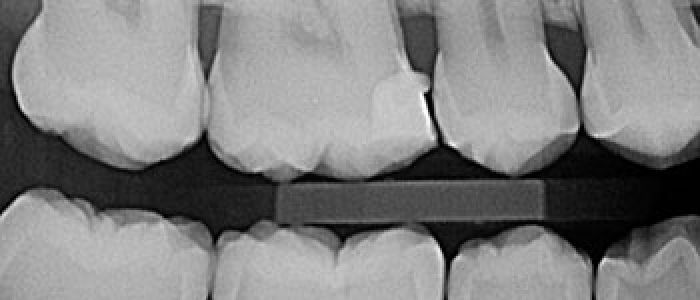

Son aquellas en las que la película se coloca en el interior de la cavidad bucal. Según el tamaño y la colocación de la película se pueden clasificar en procedimientos periapicales o retroalveolares o retroalveolares, bite wing o interproximales y oclusales.